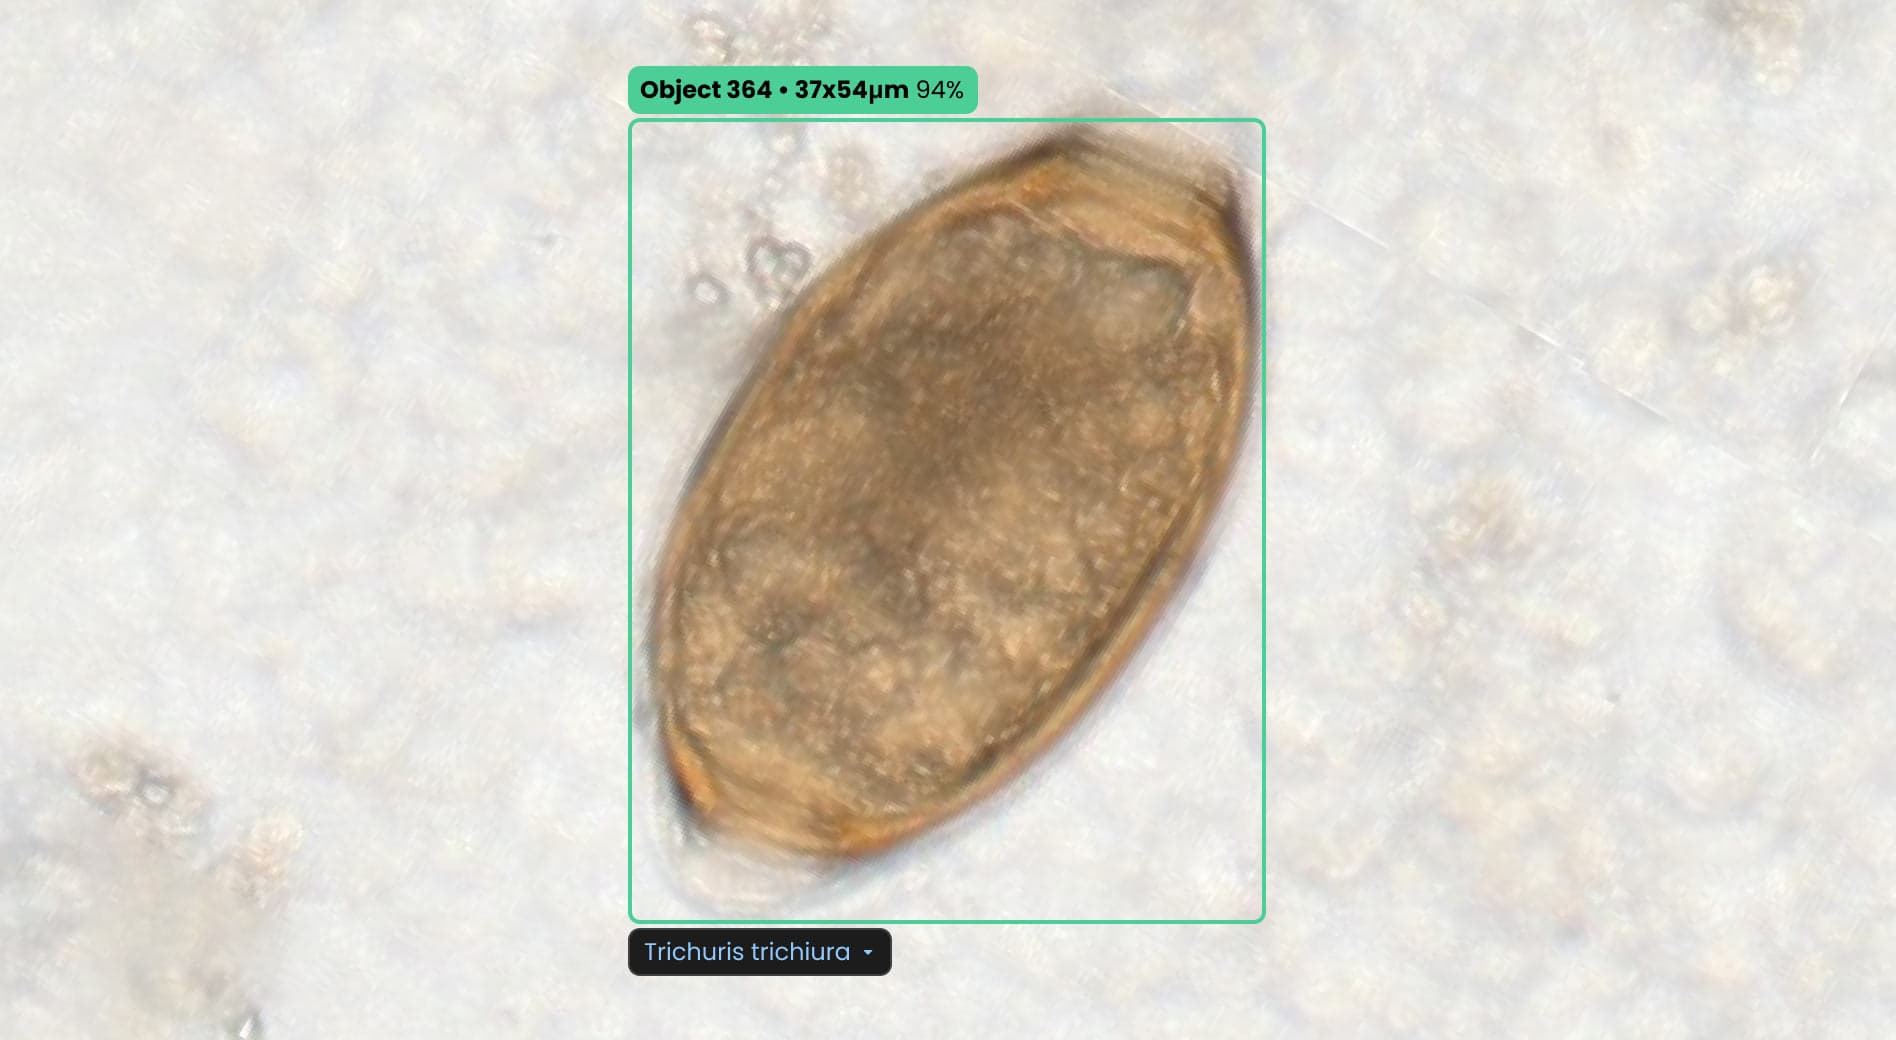

Once the data is uploaded, the AI instantly identifies parasite species. You receive visual evidence for every finding, with dimensions to confirm the identification. Simply review the AI’s results and provide the final diagnostic confirmation.